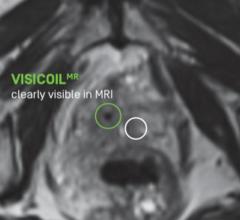

The new Visicoil MR is a helically-wound, flexible linear fiducial marker. The Visicoil MR hollow core design and ...